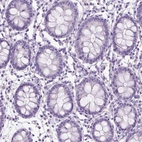

Immunohistochemistry analysis in human urinary bladder and fallopian tube tissues using HPA022261 antibody. Corresponding CYP24A1 RNA-seq data are presented for the same tissues.